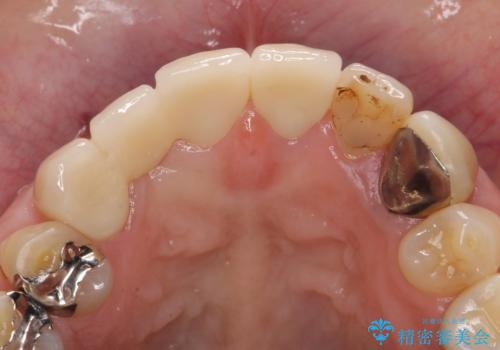

その後ブリッジによる補綴を行うことで、自然な見た目を再現することができました。

前歯の補綴ではオールセラミッククラウンを希望される患者様が多いですが、オールセラミッククラウンの中でも、エコノミー、スタンダード、スペシャル、エクセレントとランクがあります。

その中でも特に審美性が高いのがスペシャル、エクセレントです。スペシャル、エクセレントは口腔内写真をもとに熟練の技工士が、患者様の口腔内に合わせたオーダーメイドのクラウンを製作致します。